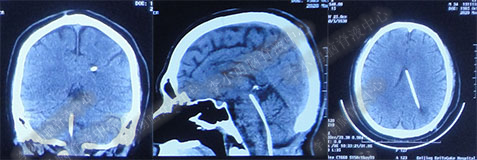

第1次内镜术后330余天即11个月(2017年4月),又开始出现头晕症状并逐渐加重。2017年6月13日(第1次内镜术后367天),行头部MRI(图-4)检查显示全脑室系统扩大。

图-4:2017年6月13日头部MRI